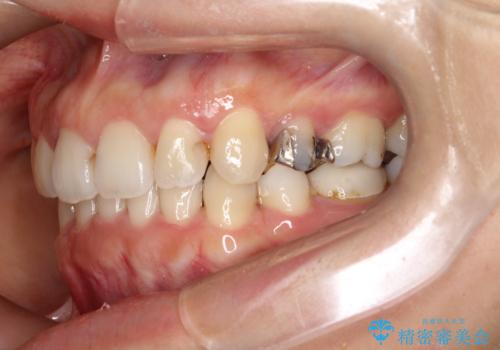

- 上下の歯の中心(正中)のズレと、口元の見た目を気にされて来院されました。精密な検査の結果、咬み合わせのバランスを整えながら、正中線を一致させる治療が必要と判断。患者様のご希望に合わせ、透明で目立ちにくいインビザライン(マウスピース矯正)による治療計画を立案しました。歯列全体を奥(遠心)へ移動させるためにゴムかけを併用。さらに、見た目を改善するため、既存の金属の被せ物をセラミッククラウンに交換することも治療計画に組み込みました。

今回の矯正治療では、透明なマウスピース型の装置インビザラインを使用しました。歯列を奥へ動かす遠心移動の効率を高めるため、患者様ご自身にゴムかけも行っていただきました。この併用によって、歯をより正確かつスムーズに動かすことができ、上下の歯の中心である正中線を一致させることが可能になりました。また、治療の最終段階では、以前から入っていた金属の被せ物を、天然歯に近い色合いのセラミッククラウンに交換。矯正治療と審美治療を組み合わせることで、機能的な咬み合わせの改善に加え、金属が見えない、より自然で美しい口元を獲得していただけました。